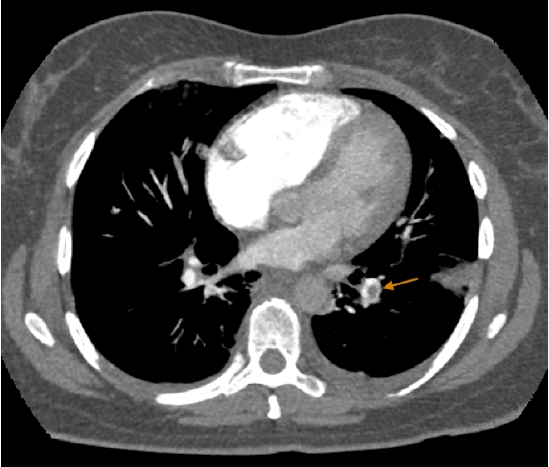

Angiotac aorta torácica y pulmonares 1 Angio 2 Estudio de tórax En primer lugar en una arteria de gran calibre identificamos 3 capas la íntima en contacto con el lumen (calcificaciones), luego la media y la más externa es la adventicia. Snowflake, 4angioTACtrombooclusivopulmonar AngioTAC #, 3 Signo de Westermarck #, img0801 #. Se realizó angiografía por tomografía axial computada (angioTAC) de arterias pulmonares, que demostró TEP bilateral, que comprometía arterias pulmonares principales, con dilatación de VD ( Figura 1 ), y reflujo del contraste hacia la vena cava inferior, hallazgos que indicaban disfunción ventricular derecha.

Sospechar un tromboembolismo pulmonar y proceder a su confirmaciónn • Las mujeres deben ser informada de los posibles efectos adversos de los anticonceptivos y su forma de presentación clínica, para poder detectarlos precozmente. TROMBOEMBOLIA PULMONAR (Clasificación de Wells (< 4 Poco probable 4 TROMBOEMBOLIA PULMONAR, s1q3t3 #, HNF IM forbidden Abscesos Frios!. O AngioTAC TEP radiológicamente masivo con signos de hipertensión pulmonar (aumento calibre arteria pulmonar y dilatación VD) 7 O Se comenta de nuevo con UCI y tras valoración del riesgo, se decide ingreso en Neumología con diagnóstico de TEP bilateral 8.